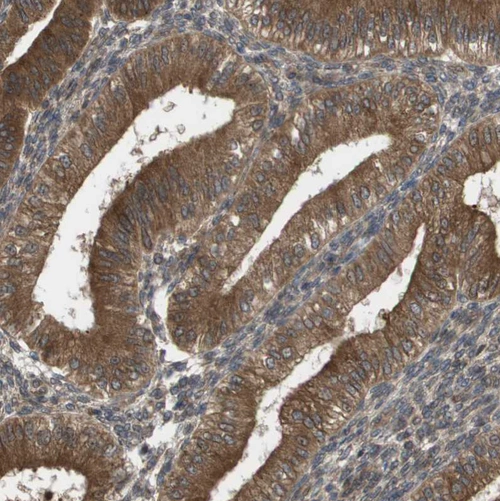

Immunohistochemical staining of human endometrium shows strong cytoplasmic positivity in glandular cells.